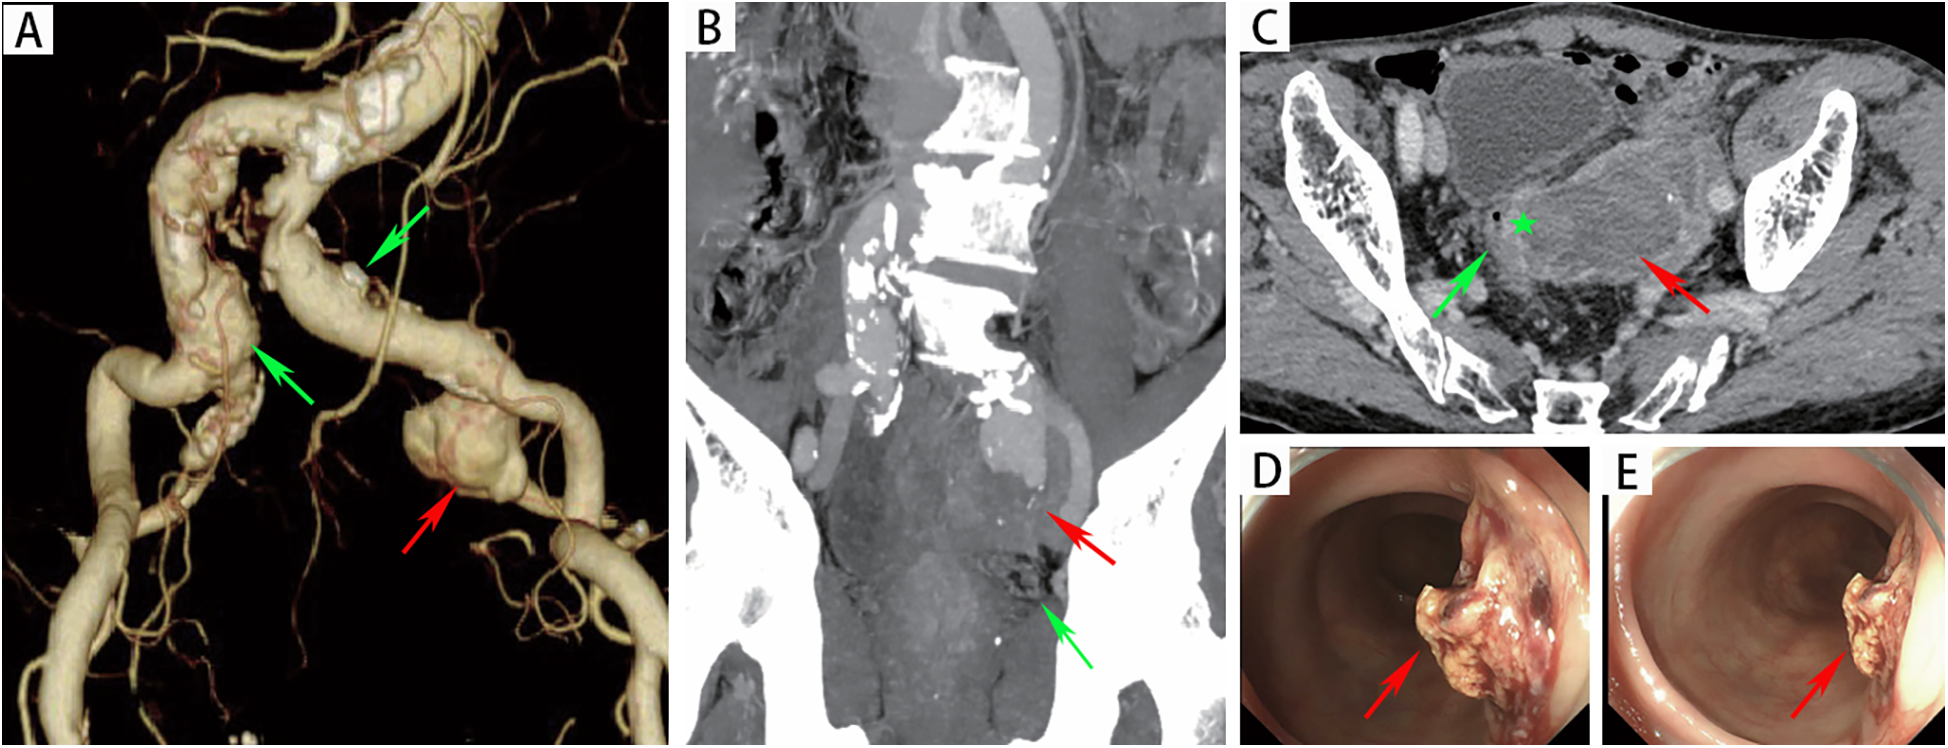

An 82-year-old male presented to the emergency department with a half-month history of intermittent hematochezia, with an estimated blood loss of 100–200 ml per episode. He also reported generalized weakness, dizziness, lower abdominal pain, and occasional passage of blood clots. The patient denied abdominal distension, diarrhea, fever, or bowel obstruction, and reported no significant recent weight change. His medical history included coronary artery disease, smoking, and COPD. There was no prior surgical or trauma history. Physical examination revealed a pulsatile mass in the left lower abdomen without significant tenderness. The extremities were cool and clammy, with poor peripheral perfusion. Vital signs on admission were: temperature 36.3°C, heart rate 122 beats/min, respiratory rate 23 breaths/min and blood pressure 115/78 mmHg. Laboratory investigations revealed anemia (hemoglobin:75 g/L; reference range: 114–154 g/L), hypoalbuminemia (albumin:25.8 g/d; reference range: 40–55 g/L), renal insufficiency (serum creatinine:1.34 mg/dl; reference range: 0.6–1.2 mg/dl) and acute heart failure (B-type natriuretic peptide: 1,125 ng/L; reference range < 226 ng/L). Other parameters were within normal limits. Computed tomographic angiography (CTA) demonstrated a 32 × 27 mm right common iliac artery aneurysm and a 20 × 27 mm left common iliac artery aneurysm. A 66 × 51 mm aneurysm was identified in the left internal iliac artery with extensive intramural thrombus (Figure 1A). Furthermore, the rectal wall showed irregular thickening with focal discontinuity along the left upper wall (Figures 1B,C), suggestive of a fistula between the left internal iliac artery aneurysm and the rectum. Emergency colonoscopy revealed an ulcer with active bleeding at 13 cm from the anal verge (Figures 1D,E); a biopsy of the surrounding tissue was obtained. The patient was diagnosed with: (1) left internal iliac artery–rectal fistula; (2) hemorrhagic shock; (3) hypoalbuminemia; (4) renal insufficiency; (5) coronary artery disease; (6) acute heart failure and (7) COPD.

Figure 1

(A) CTA revealed a left internal iliac aneurysm (red arrow) and bilateral common iliac artery aneurysms (green arrow). (B) The red arrow indicated the left internal iliac artery aneurysm, with the rectum (green arrow) located below it. (C) CTA revealed that there was an unclear boundary between the left internal iliac artery aneurysm (red arrow) and the rectal wall (green pentagon). (D-E) Endoscopic evaluation revealed a raised, blood clot-adherent ulcer (arrows) on the rectal lateral wall.